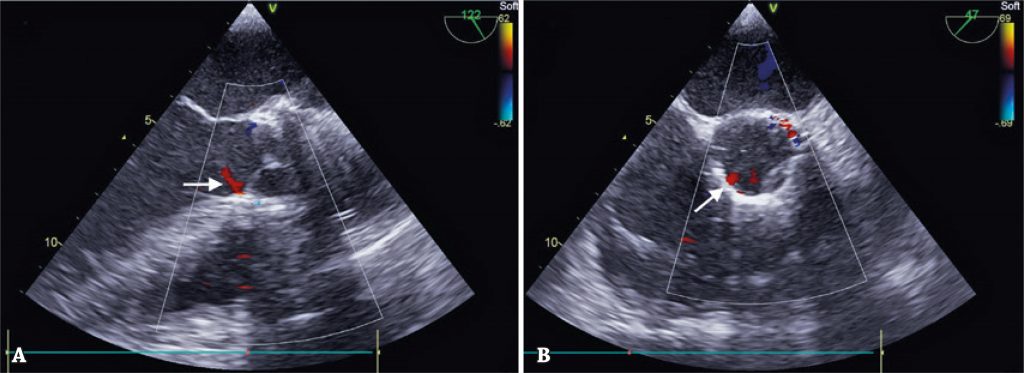

Figure 4

Echocardiographic result. Arrow indicating trivial paraprosthetic regurgitation. (A) Long axis of aorta. (B) Transverse axis of aorta.